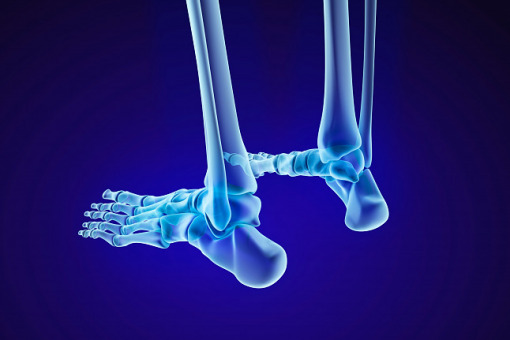

Jedyny w Polsce ośrodek szkoleniowy leczenia złamań kości piętowej powstał w ostrowskim szpitalu

W tym roku mija 10 lat od przeprowadzenia na oddziale ortopedii i traumatologii narządu ruchu w szpitalu w Ostrowie Wlkp., pod kierownictwem dr. Mirosława Falisa, pierwszej w Polsce operacji zespolenia złamania kości piętowej gwoździem śródszpikowym Calcaneal. Od tego czasu wykonano 650 operacji z wykorzystaniem tej metody.